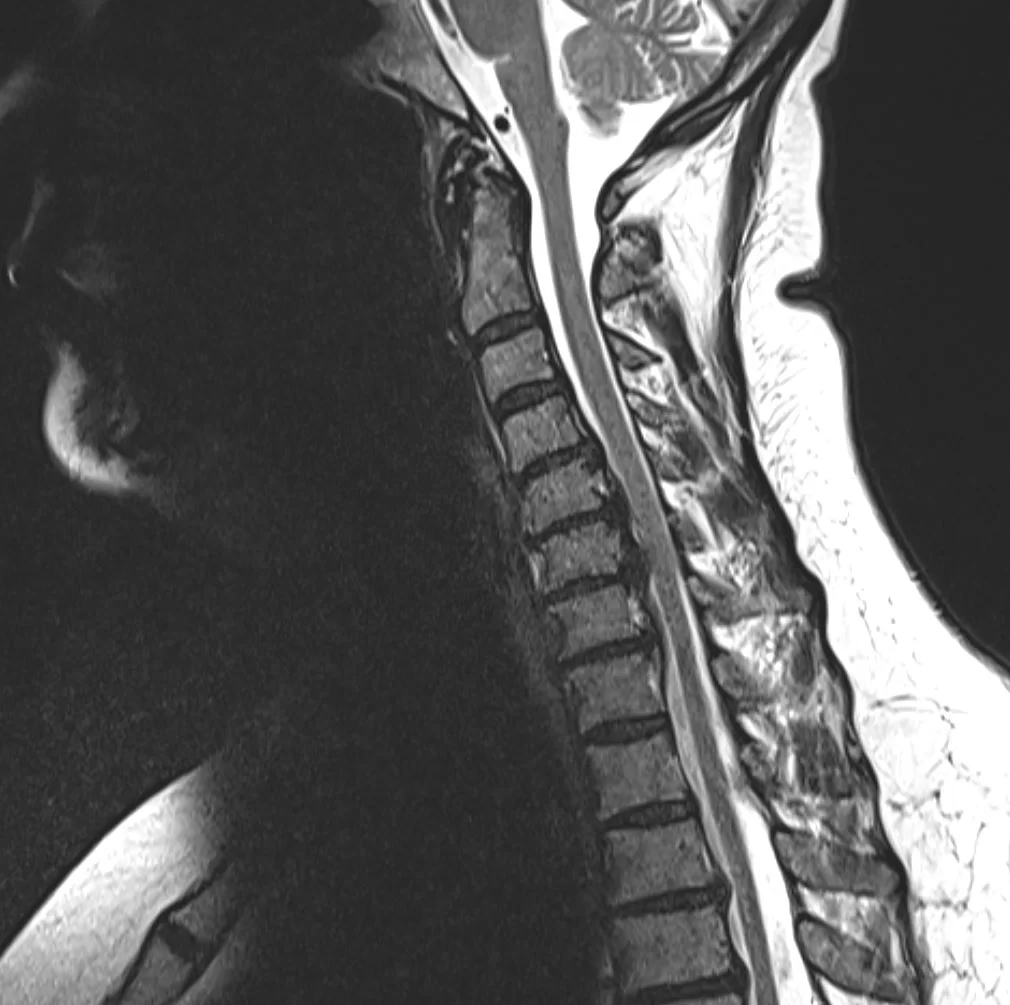

Ασθενής γυναίκα 57 ετών με αιμωδίες αριστερού άνω άκρου, αυχεναλγία και διαταραχή βάδισης.

Ο απεικονιστικός έλεγχος έλεγχος με μαγνητική και αξονική τομογραφία της αυχενικής μοίρας της σπονδυλικής στήλης ανέδειξε σημαντική εκφύλιση της αυχενικής μοίρας της σπονδυλικής στήλης με πολυεπίπεδη στένωση λόγω εκτεταμένης οστεφύτωσης και επασβέστωσης του οπισθίου επιμήκους συνδέσμου.